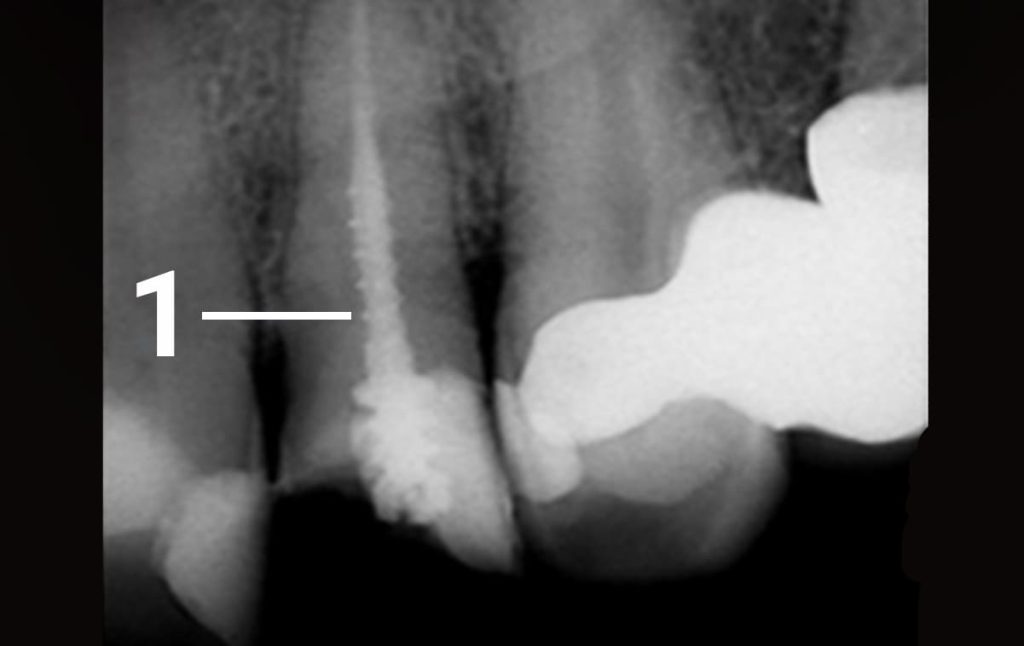

1. A 50-year old patient contacted our clinic complaining of a crack in a filling located in his upper jaw which appeared following an injury. The tooth was previously treated in a different clinic. Following an inspection of the tooth, it was decided that the root canal needed to be treated again. 1 - metallic pin in the tooth canal